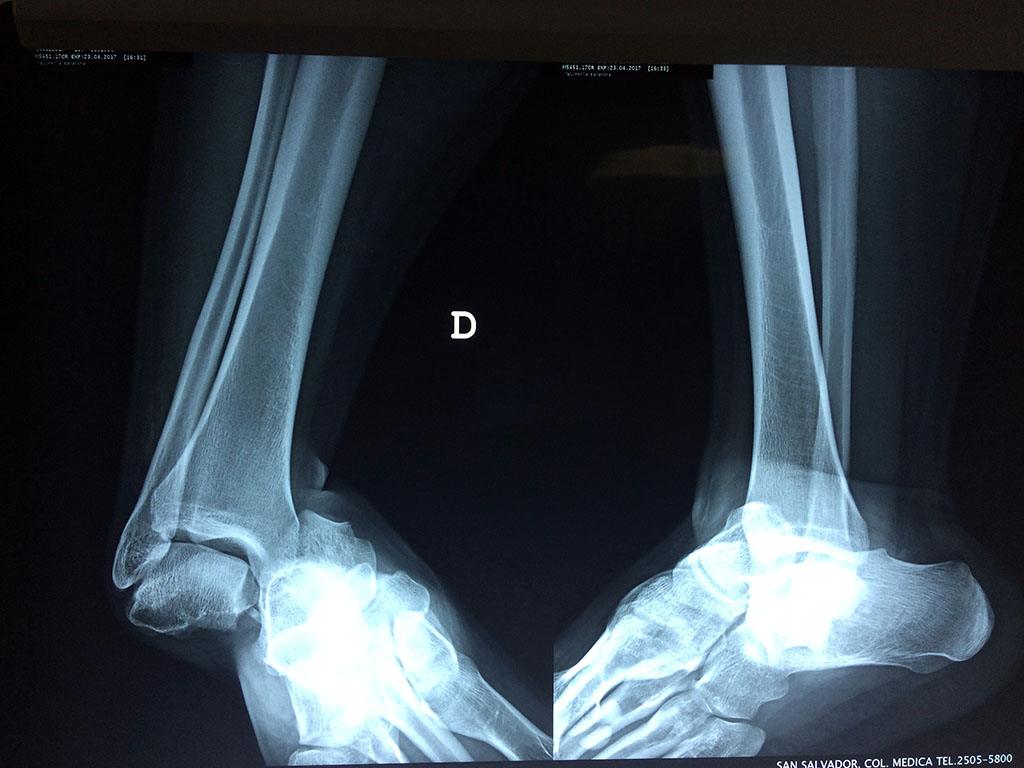

Una fractura de tobillo es la rotura de uno o más de los huesos del tobillo. Estas fracturas pueden ser:

- Completas (el hueso está perforado y está en 2 partes).

- Los extremos de los huesos están desalineados entre sí (desplazados).